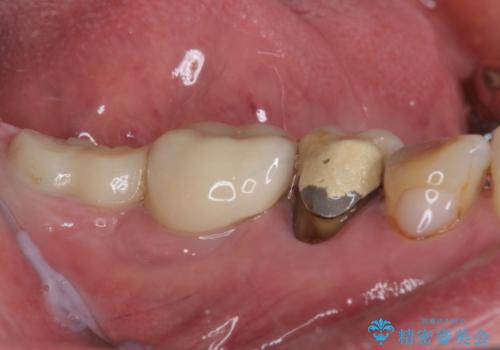

- 前歯に穴が空いてしまったとのことで来院された患者様です。

変色が気になっていたものの歯医者が怖くて来院を躊躇されていたそうです。

歯髄は既に壊死していたため、根管治療を行い、その後オールセラミッククラウンにて補綴することとしました。

審美障害が著しかったため、速やかに仮歯に置き換え、その後根管治療を行いました。根尖部の骨透過像が大きかったので、定期的にレントゲン写真を撮影し、1年後には有意に縮小していることが確認できました。